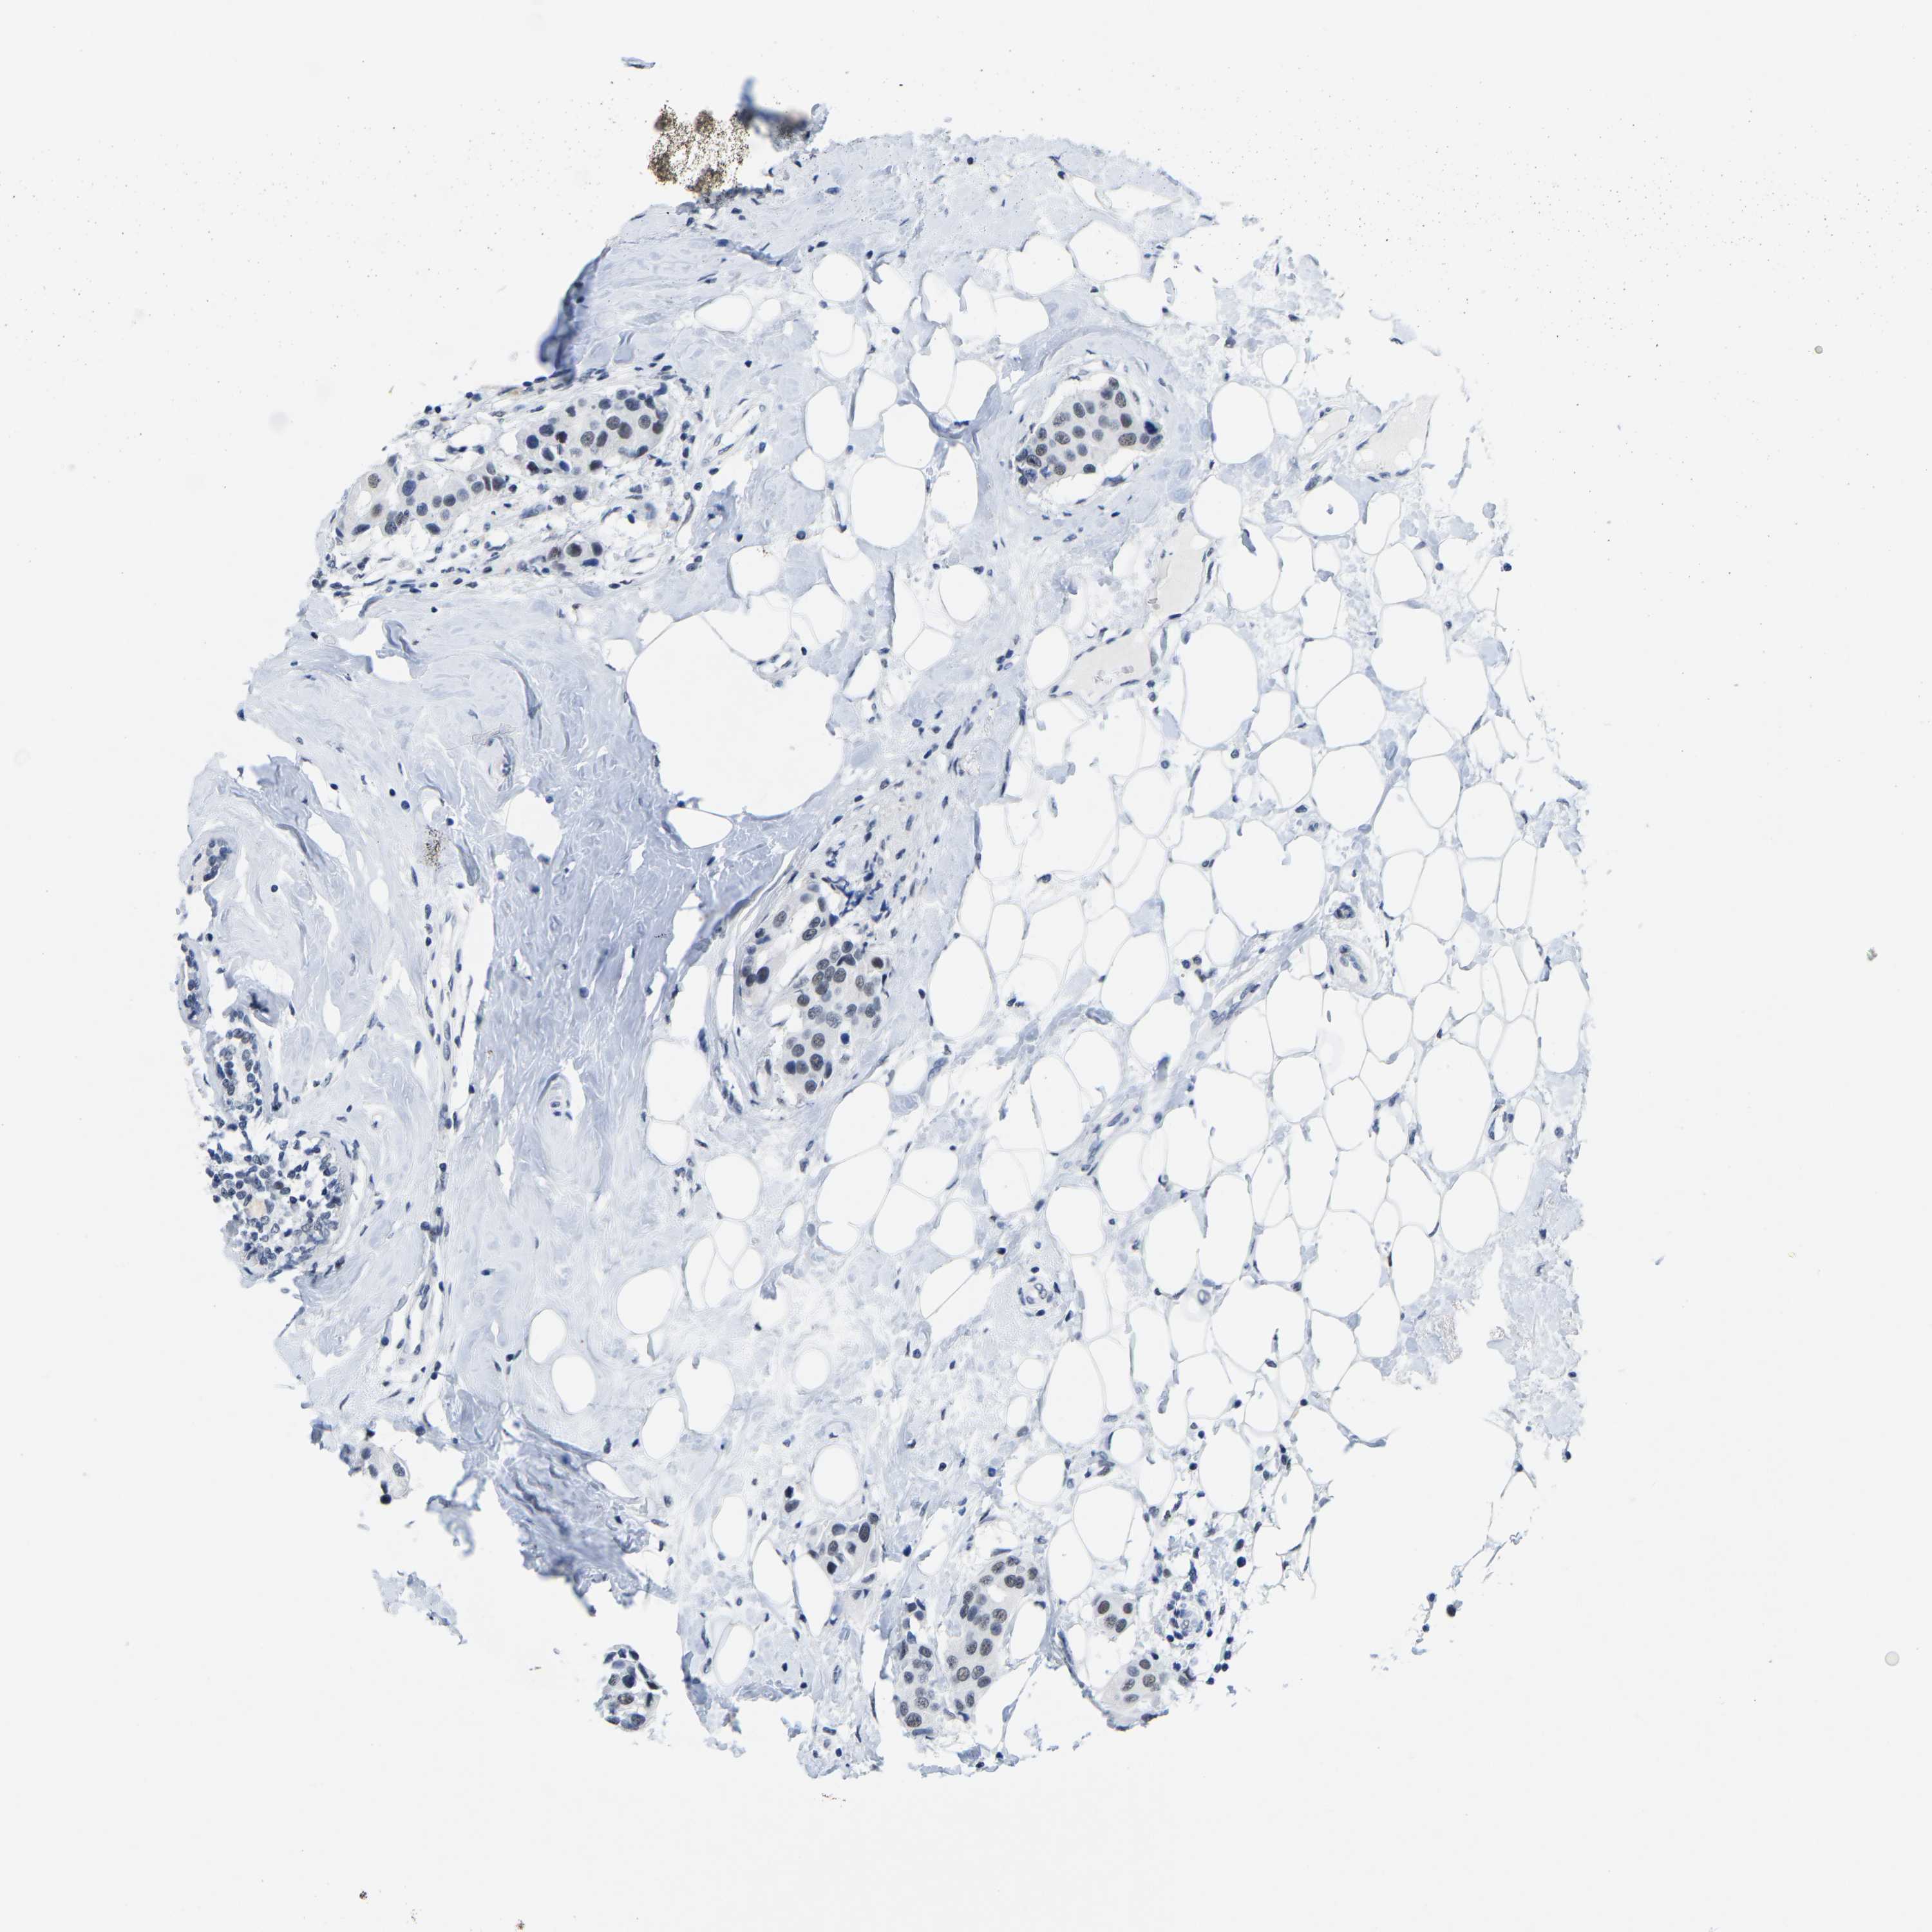

CANCER BREAST CANCER Show tissue menu

BRCA TCGA BRCA VALIDATION PROTEIN EXPRESSION